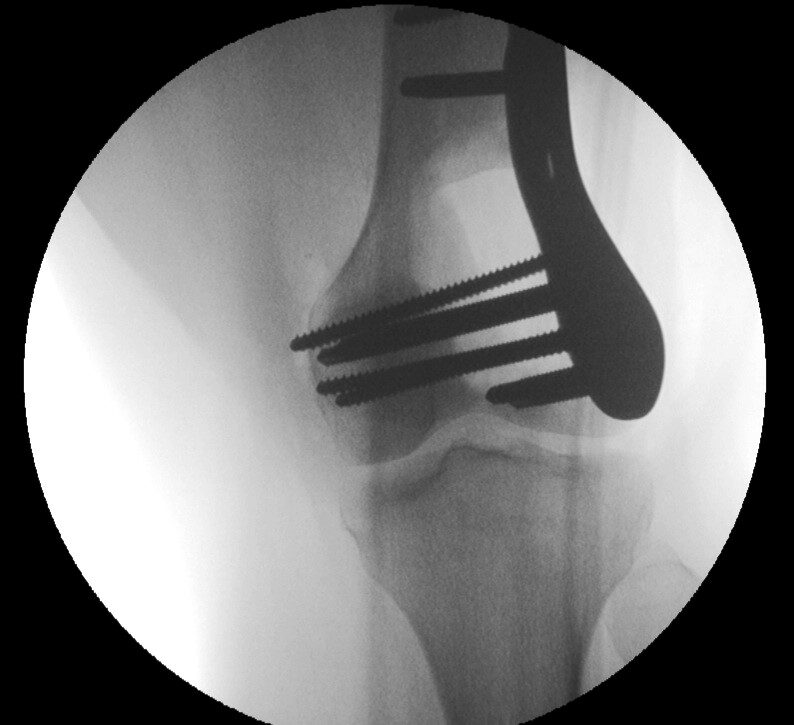

Plain x-ray

• Radiographs of low grade intraosseous osteosarcoma may demonstrate a benign appearance (Fig. 1 & 2).

• However, most lesions show intramedullary extension, cortical violation, and soft tissue involvement.

• The majority arise centrally in the bone, from the medullary cavity and more frequently are methaphyseal.

Fig. 1

Fig. 2

Fig. 1 & 2: Plain X Ray of Low Grade Intraosseous Osteosarcoma. AP (Fig. 1) and Lateral (Fig. 2) view of the left knee, shows a mixed sclerotic-lytic lesion in the supracondylar area of the femur. There is no periosteal reaction, cortical destruction, or extraosseous soft tissue mass. The lesion is fairly well circumscribed with a sclerotic margin. The lesion deceptively looks benign